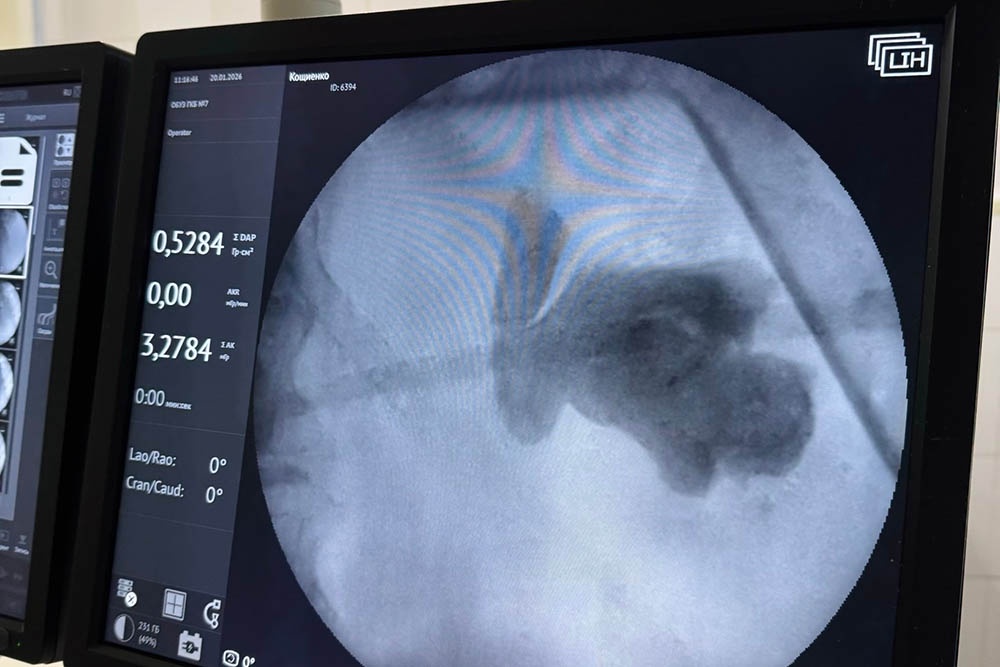

- Учитывая клиническую сложность ситуации, было принято решение о проведении комбинированной хирургической операции малоинвазивными методами. Одномоментно выполнена гибкая лазерная уретеролитотрипсия (дробление камня в мочеточнике через естественные пути) и пункционная нефролитотрипсия (дробление и удаление камня через небольшой прокол в поясничной области), - рассказал врач-уролог высшей квалификационной категории ГКБ N 7 в Иванове Дмитрий Болдин.

Хирурги не просто восстановили отток урины , но и добились статуса "stone-free", то есть полностью освободили мочевыводящие пути от конкрементов. В медицинской практике такой результат при камнях столь большого объема - редкость.